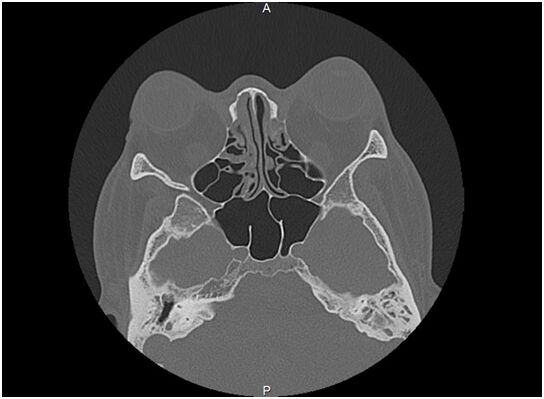

小龙曾到多家医院检查,检查发现他有鼻咽部肿物,肿物挤压了咽鼓管口,必须要手术切除鼻咽部的肿物。同时,小龙还患有严重的鼻中隔偏曲,鼻中隔偏曲加上鼻咽部肿物、扁桃体肥大使得小龙的上呼吸道堵塞,引发严重的鼾症。有好几次,小龙都被推进了手术室准备手术,但是由于他患有严重的甲亢,心功能受到一定影响,手术及麻醉风险较大,几次又被推回病房。

6月3日,在麻醉医师的密切配合下,中山大学附属第七医院耳鼻喉科主任樊韵平教授主刀为小龙做了手术。经过两个多小时,医生们通过鼻内镜切除了鼻咽部肿物以及肿大的双侧扁桃体,同时通过耳内镜在双耳鼓膜放置了通气引流管。手术很成功,没有出现手术并发症等风险。小龙术后恢复很好,打鼾的症状基本消失,听力也恢复了。出院后,小龙还需要一段时间休养,并继续用药控制甲亢。

原来堵住小龙咽鼓管的肿物叫腺样体,也叫咽扁桃体或增殖体,位于鼻咽部顶部与咽后壁处,属于淋巴组织,表面呈桔瓣样。腺样体和扁桃体一样,出生后随着年龄的增长而逐渐长大,4-6岁时为增殖最旺盛的时期,青春期以后逐渐萎缩。

小龙就是因为腺样体肥大堵住咽鼓管导致了一系列症状。无独有偶,5岁的小志(化名)睡觉呼噜打得震天响,开始家人并不在意,还以为是遗传,可是后来发现小志常常把脸憋的通红,可把家人吓坏了。到医院检查,发现是腺样体和扁桃体肥大,已经堵塞了大部分后鼻孔和咽鼓管,再不做手术,就会引起很多问题,孩子也可能会呈现“腺样体面容”。孩子长期打鼾,用嘴呼吸要引起家长的注意,否则形成腺样体面容后就很难改变,将影响到孩子以后的身心健康成长。